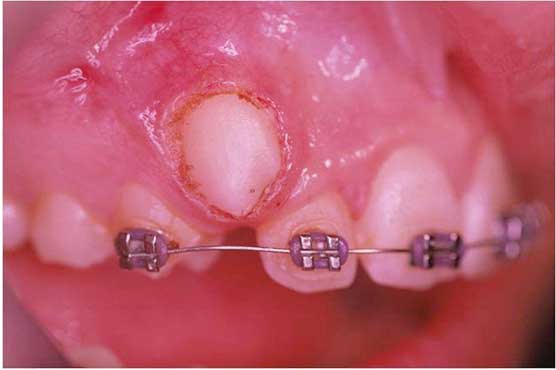

1. Αποκάλυψη έγκλειστου κυνόδοντα:

Νεαρός ασθενής που βρισκόταν υπό ορθοδοντική θεραπεία εμφάνιζε έγκλειστο τον κυνόδοντα άνω αριστερά.

Με τη χρήση του Nd-Yag laser έγινε αποκάλυψη του κυνόδοντα, ώστε να γίνει δυνατή η ορθοδοντική μετακίνηση (μετοποθέτηση αγκυλίου-Bracket)

ΑΠΟΚΑΛΥΨΗ ΕΓKΛEIΣΤΟΥ ΚΥΝΟΔΟΝΤΑ

Αρχική κλινική εικόνα

Μετά την αποκάλυψη